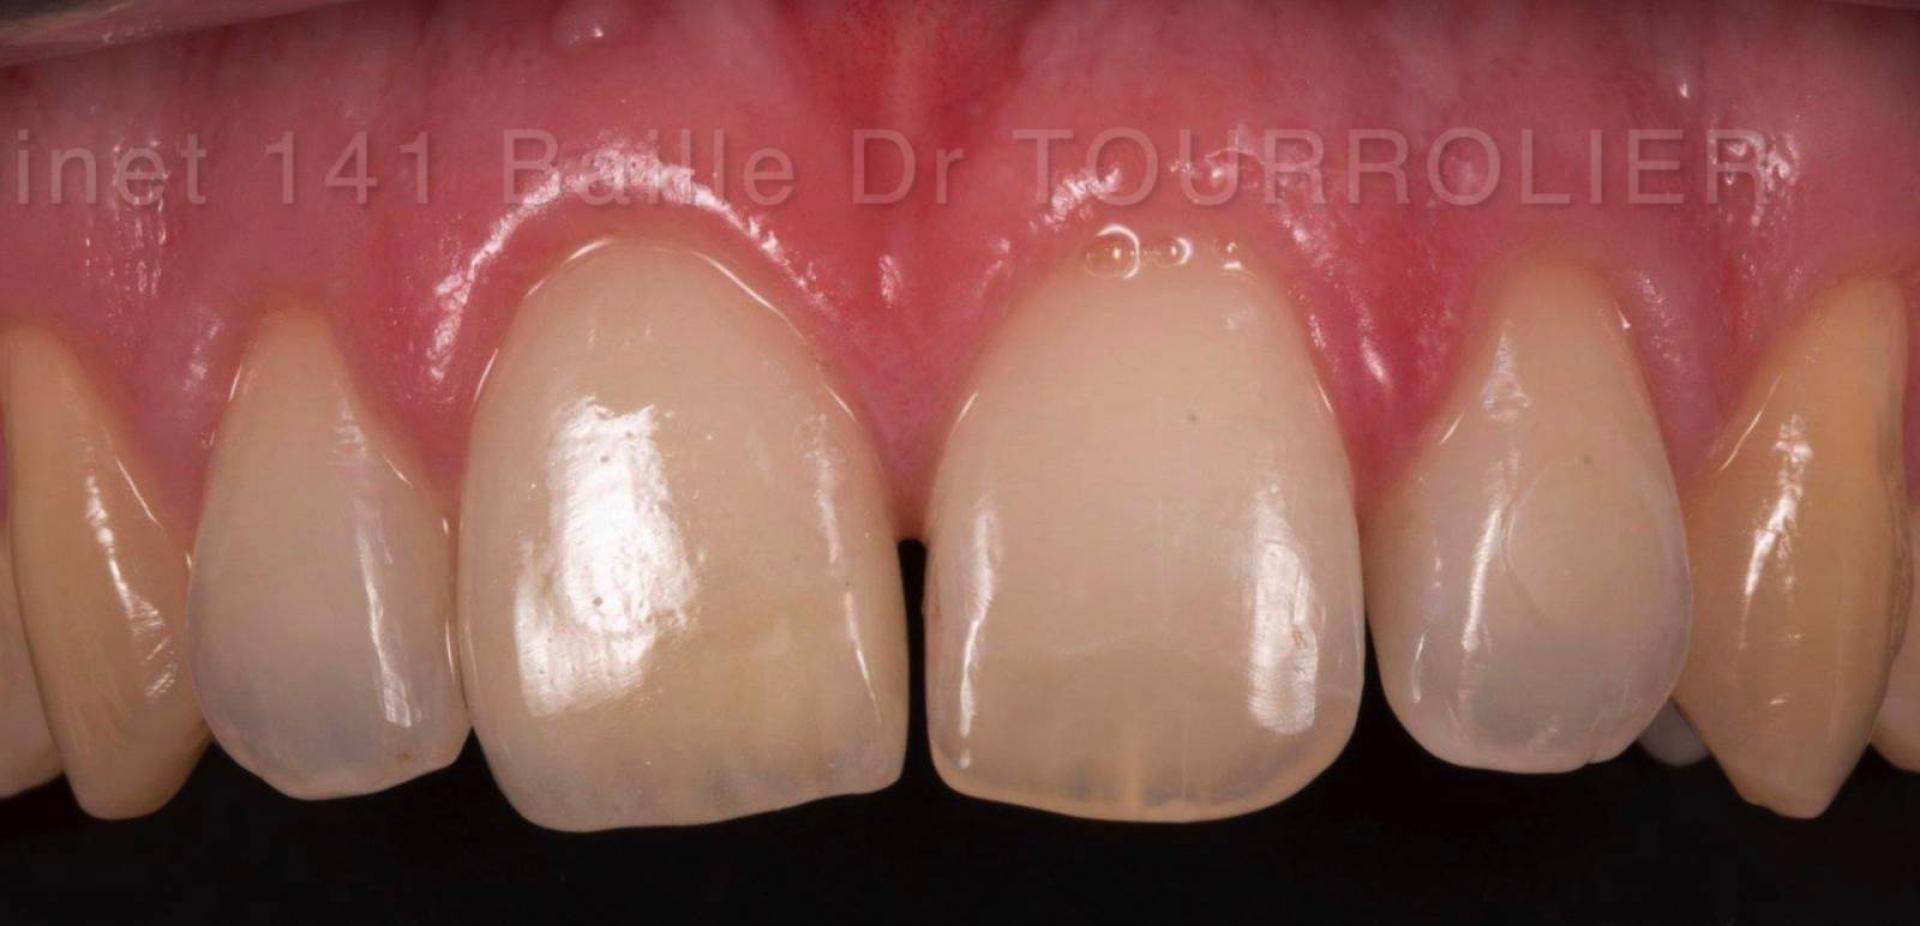

Comment avoir une idée du sourire final que j'aurai en fin  de traitement ?

Dans notre cabinet, nous mettons en œuvre la technique du MOKE-UP esthétique. Votre praticien établira une maquette de votre sourire final et vous placera celle-ci en bouche pour une évaluation de plusieurs jours.

Vous pourrez alors la tester sous différents éclairages, en différentes situations, valider que votre phonation n'est pas perturbée et surtout en discuter avec vos proches intimes pour avoir un avis éclairé. La notion d'esthétique est très subjective.

La référence en matière de résultat esthétique pour les facettes dentaires est de mettre en œuvre comme dans notre cabinet les facettes pelliculaires stratifiées céramiques comme les facettes Emax® que nous utilisons.